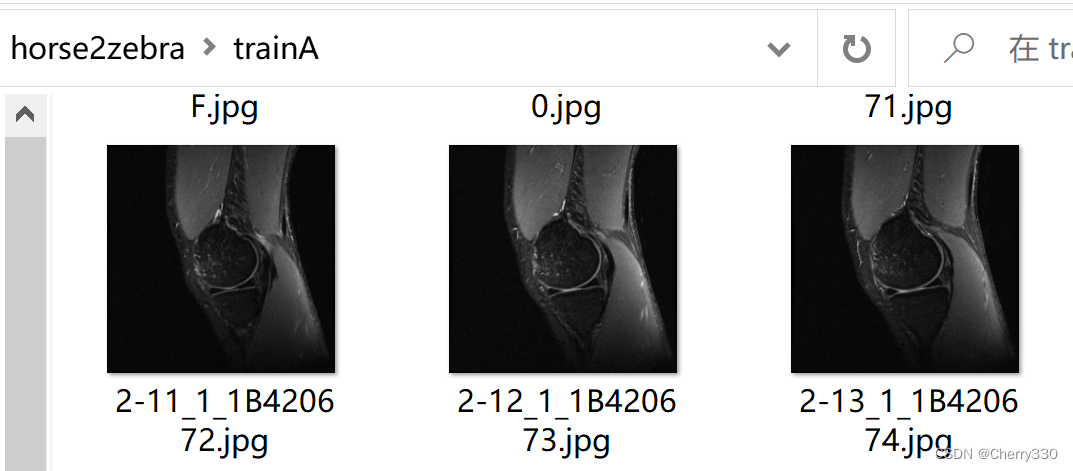

需要注意的是,trainA和trainB是训练的数据集,testA和testB是测试的数据集,大家记得按照自己需求进行分配哦~ trainA和testA是需要转换的图片,就是我做的这个的T2图片,trainB和testB是风格图片,就是我的任务中的T1图片。如图5。

图5 数据集构成